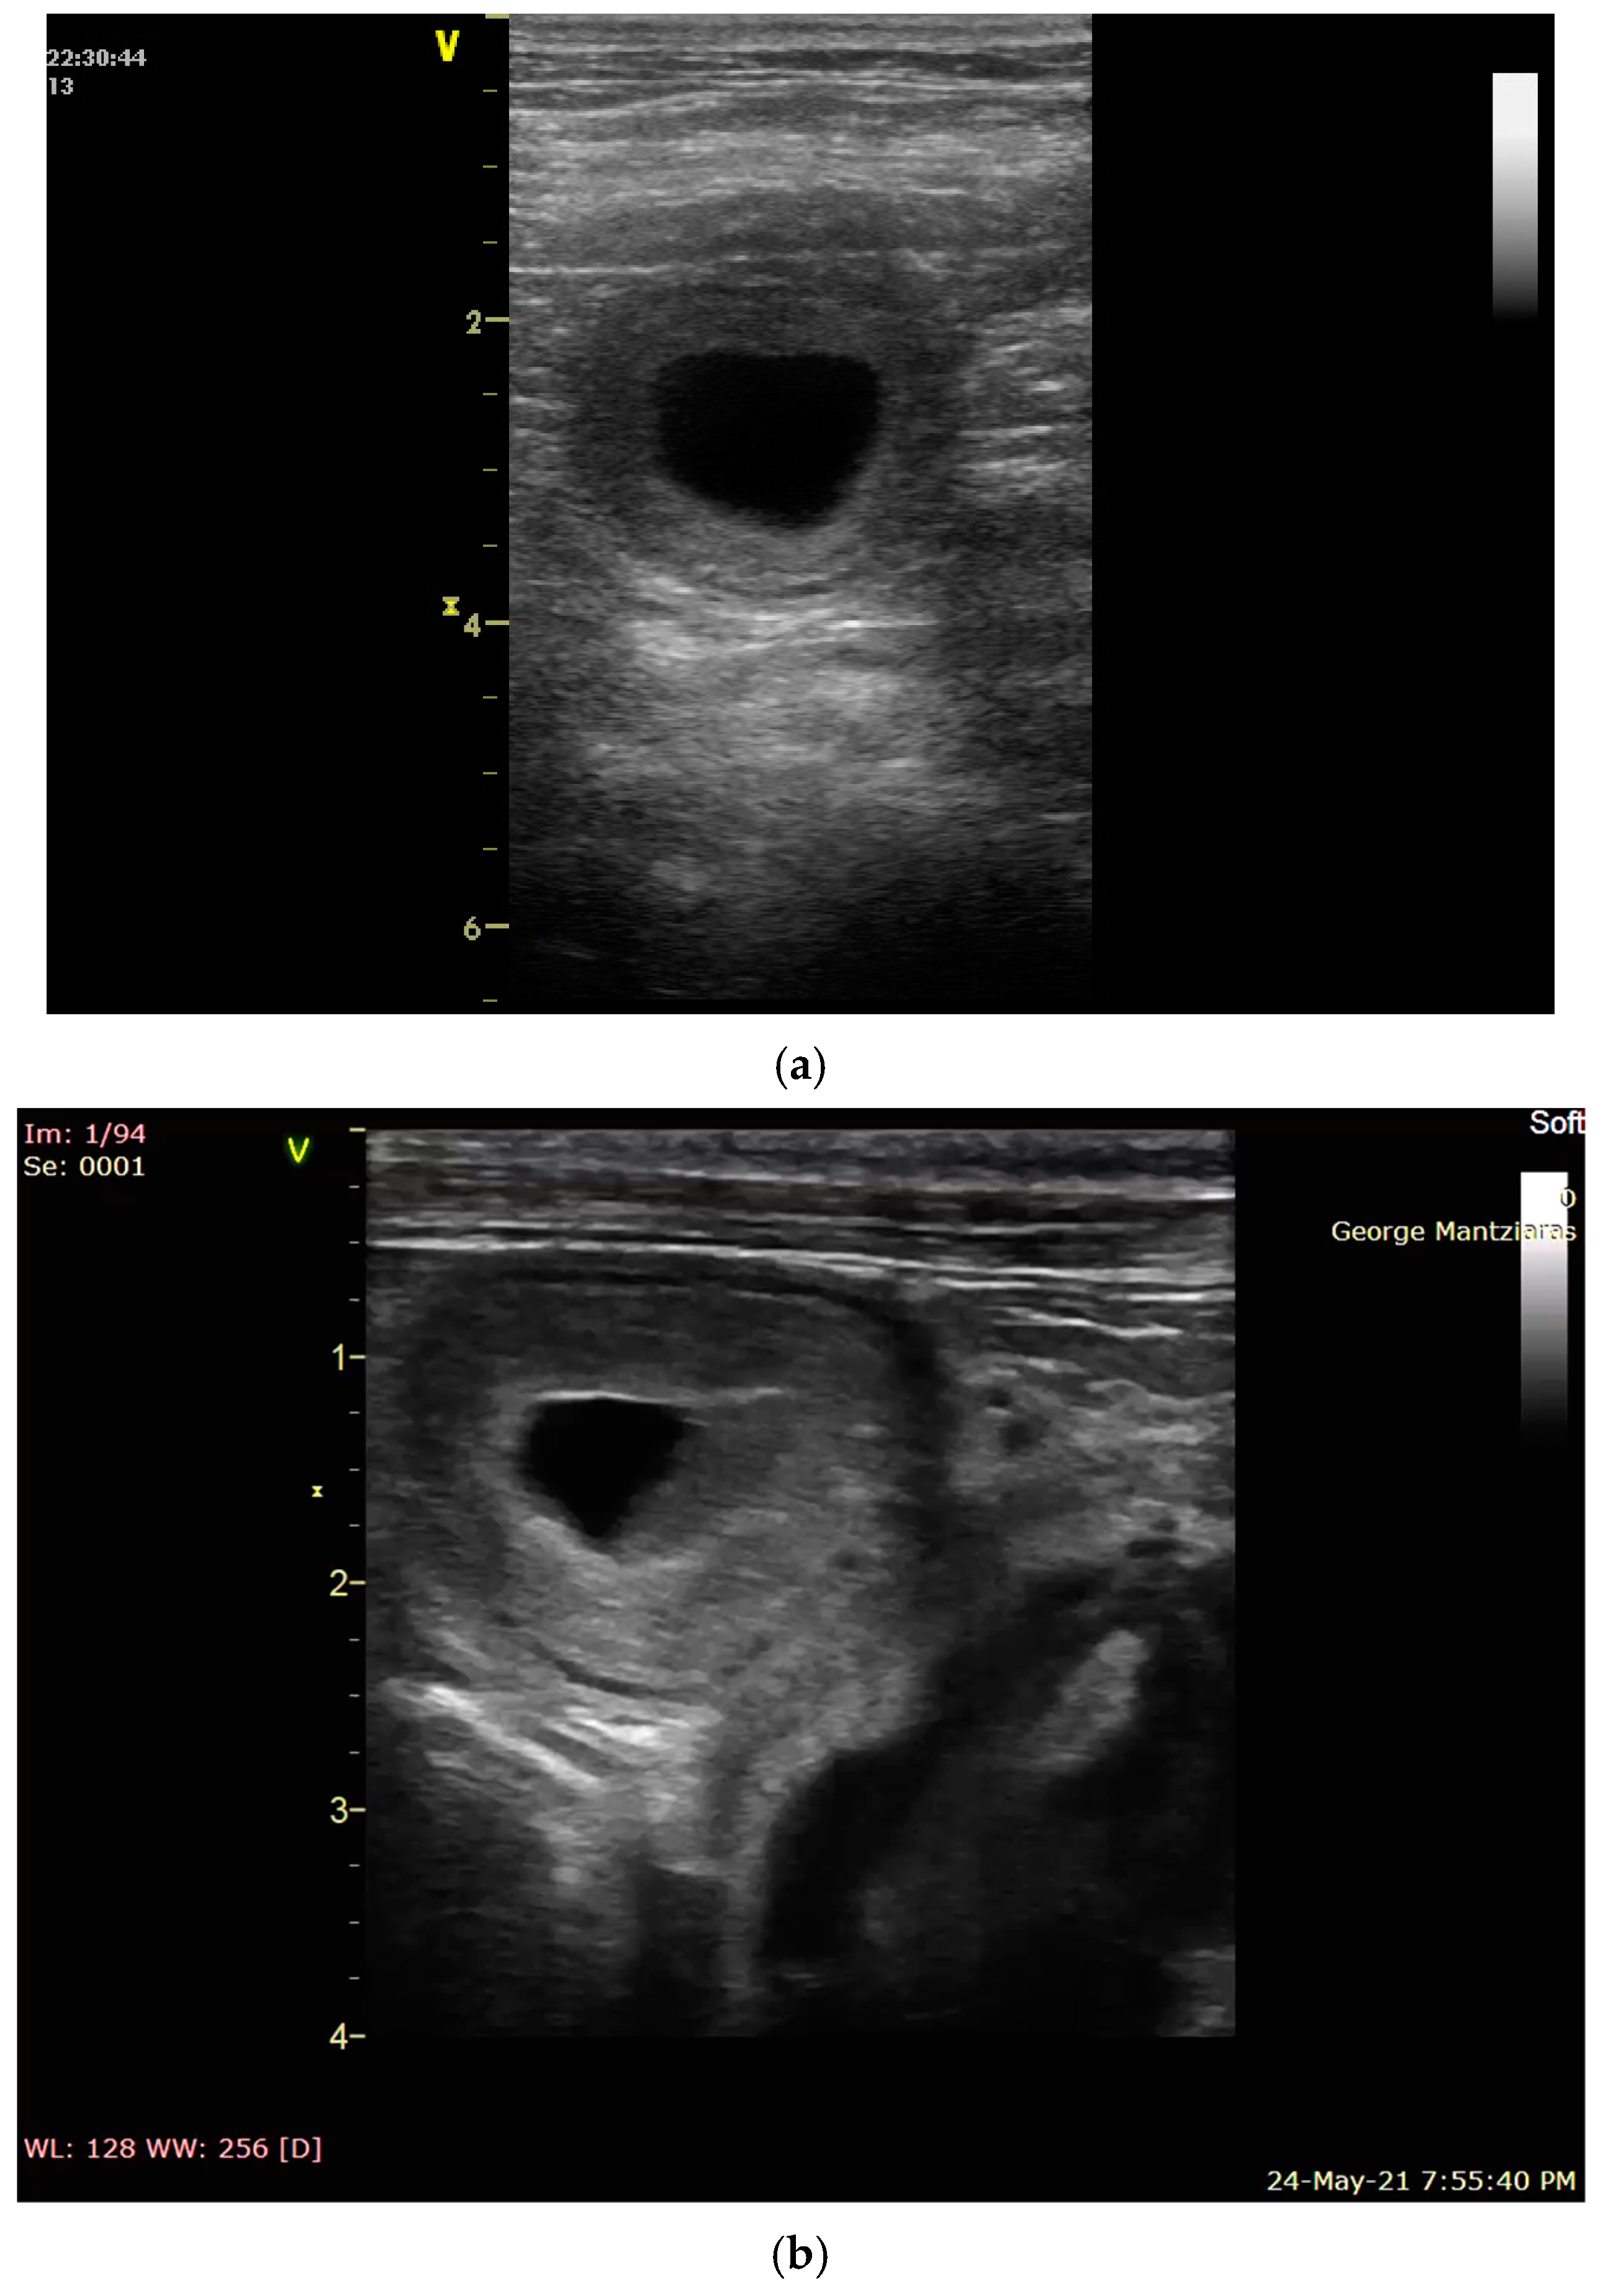

- Bigliardi, E.; Parmigiani, E.; Cavirani, S.; Luppi, A.; Bonati, L.; Corradi, A. Ultrasonography and Cystic Hyperplasia-Pyometra Complex in the Bitch. Reprod. Domest. Anim. 2004, 39, 136–140. [Google Scholar] [CrossRef] [PubMed]

- Quartuccio, M.; Liotta, L.; Cristarella, S.; Lanteri, G.; Ieni, A.; D’Arrigo, T.; De Majo, M. Contrast-Enhanced Ultrasound in Cystic Endometrial Hyperplasia–Pyometra Complex in the Bitch: A Preliminary Study. Animals 2020, 10, 1368. [Google Scholar] [CrossRef] [PubMed]

- Younis, M.; Mohammed, F.F.; Ragab, R.S.; Gohar, H.M. Ultrasonography and Pathological Evaluation of Cystic Endometrial Hyperplasia Pyometra Complex in Bitches and Queens with Related Ovarian Alterations. Glob. Vet. 2014, 13, 60–67. [Google Scholar]